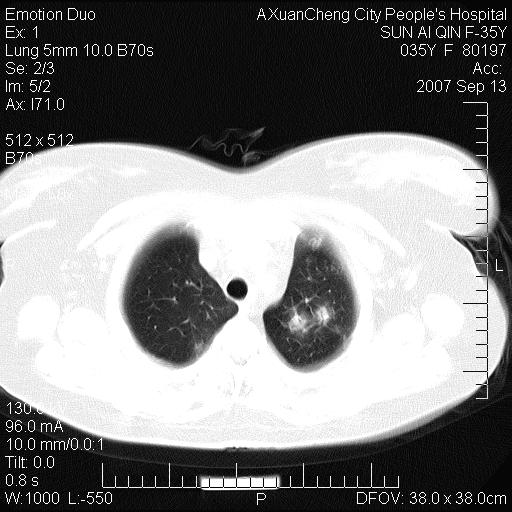

以下是引用天南地北在2007-9-13 13:43:00的发言:[br]考虑双肺、肺门侵润

以下是引用ydx_74在2007-9-13 15:42:00的发言:[br]仅看片,考虑右上肺癌并双肺转移,结合病史,考虑肺门、肺内淋巴侵润

以下是引用同在2007-9-13 15:08:00的发言:[br]支持肺门及双肺侵润.